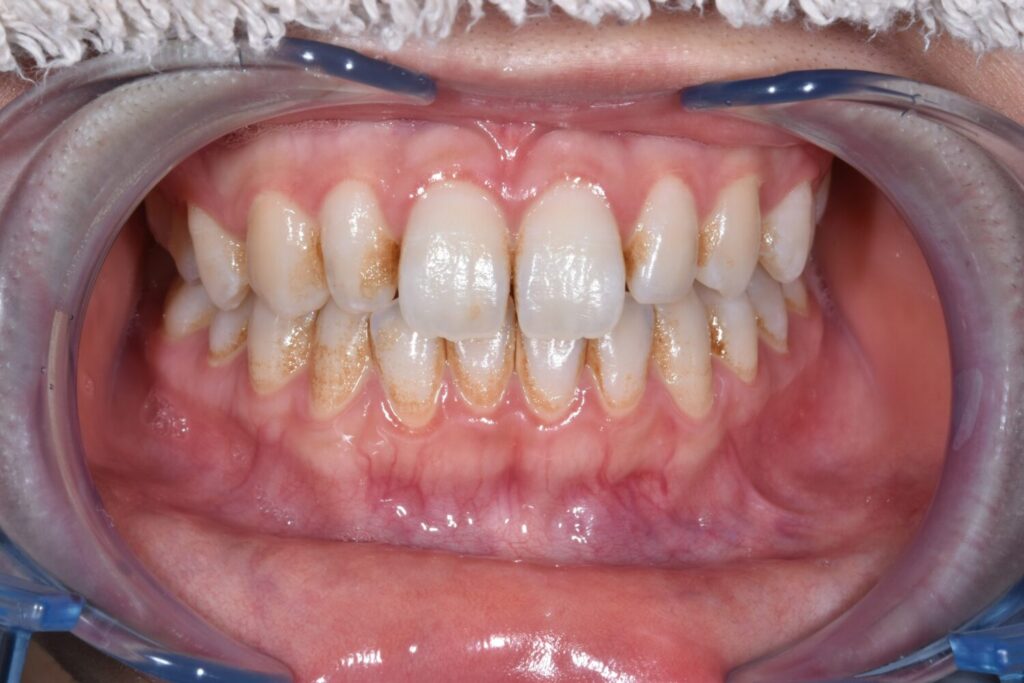

術前

毎月定期的な検診・クリーニングに来てくださっている10代の患者様

保険内のクリーニングでは落としきれない着色汚れをリフレッシュケアで改善されました。

リフレッシュケア+オプション(二次研磨:リナメルトリートメント)

¥9900+¥1100(オプション)